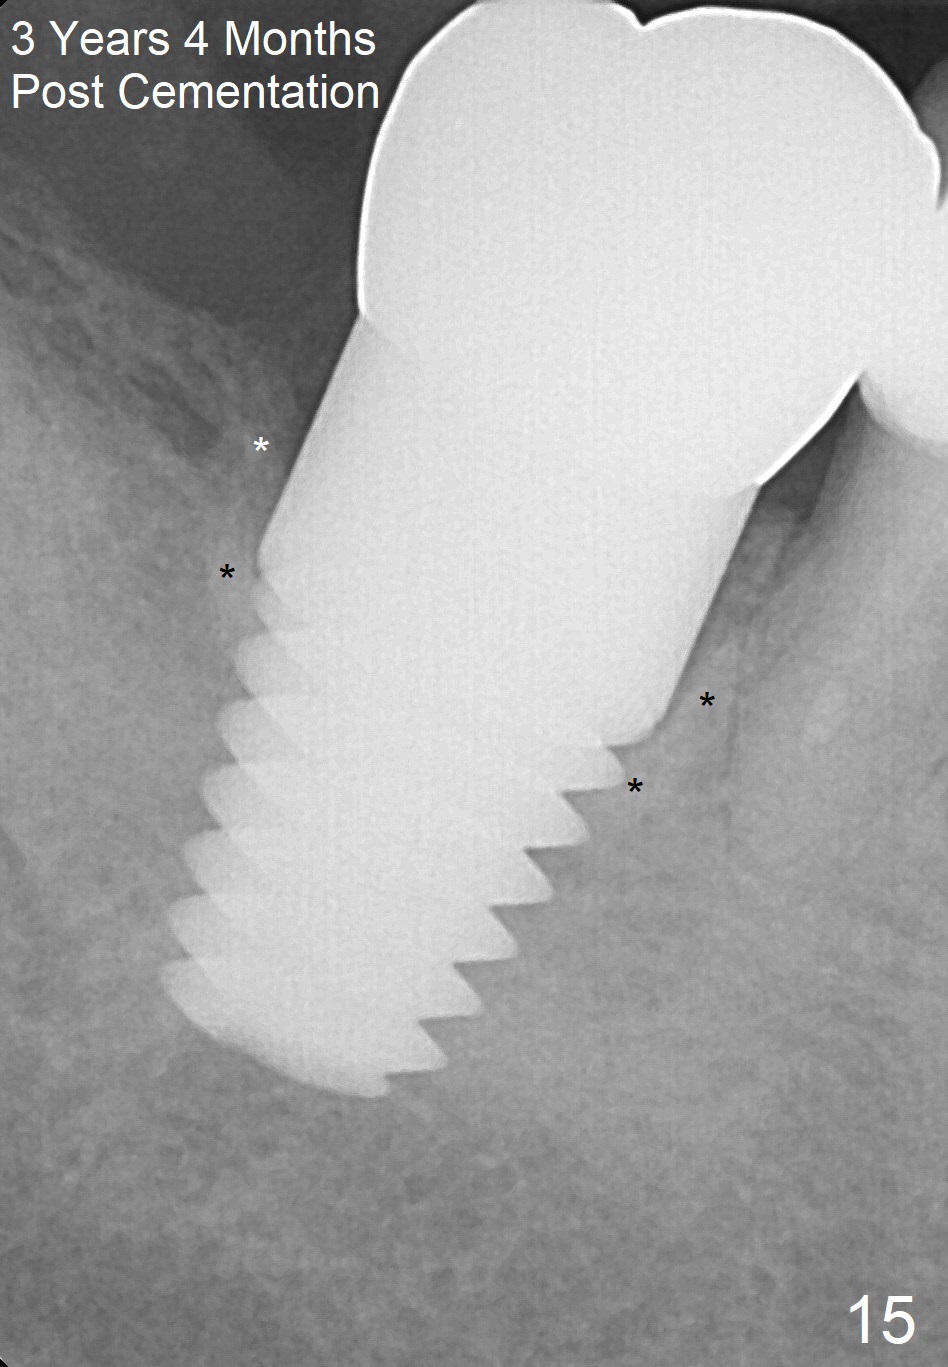

The patient returns for final restoration 5.5 months postop; it appears that the distal gap has disappeared (Fig.13 *). There is no bone loss 26 months post cementation (Fig.14). The lamina dura-like dense bone forms coronally 3 years 4 months post cementation (Fig.15 *). The 8 mm implant remains buried in the bone 5 years 4 months post cementation (Fig.16).